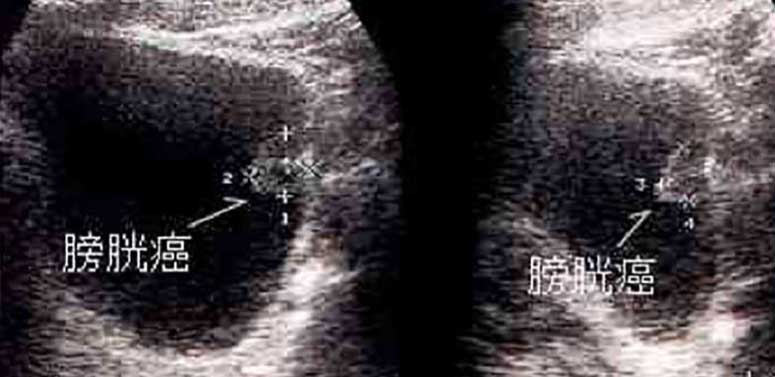

腹部超音波検査

X線を使わず痛みを伴うこともないので健康診断や人間ドックなどの初期検査でよく行われます。一般的には膀胱内に突出するような腫瘍を確認することができます。

膀胱がんの腹部超音波検査画像